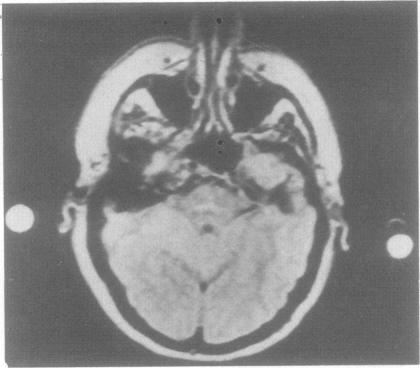

Magnetic resonance imaging (MRI) was performed in two patients in whom a clinical diagnosis of central pontine myelinolysis (CPM) had been made. MRI showed lesions in the pons in both cases about 2 years after the illness, at a time when the spastic quadriparesis and pseudobulbar palsy had recovered. The persisting abnormal signals in CPM are likely to be due to fibrillary gliosis. Persistence of lesions on MRI means that the diagnosis of CPM may be electively, after the acute illness has resolved.